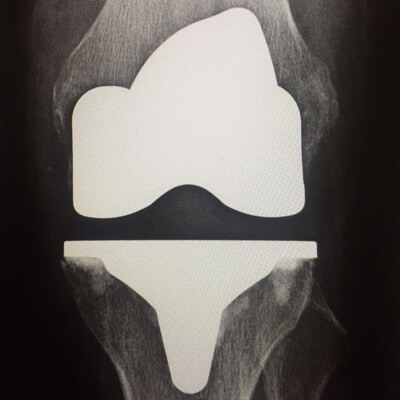

LE GENOU

Arthroplastie

Remplacement prothétique des surfaces de l'articulation du genou ( prothèse totale de genou, prothèse unicompartimentale ).

Pour la recherche d’une pathologie méniscale ou ligamentaire chez l’adulte jeune , l’IRM (imagerie par résonance magnétique) est l’examen de choix. Pour un bilan concernant l’arthrose de genou (gonarthrose) des radiographies sont plus intéressantes et idéalement des clichés « en charge »(shuss).